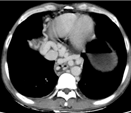

术中图像